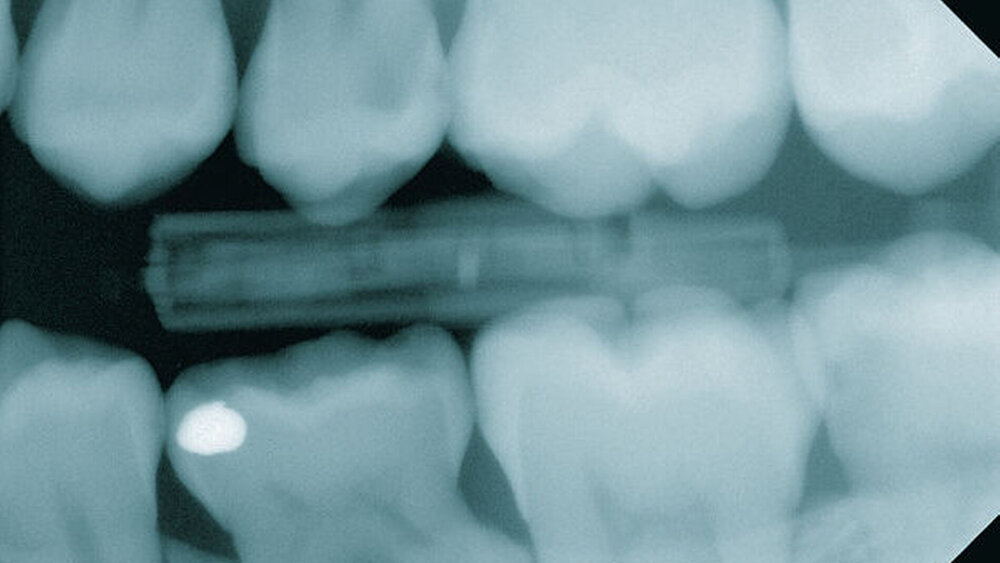

Methoden der Kariesdiagnostik – abhängig von der Zahnfläche

Bei der klinischen Kariesdiagnostik im Approximalraum lag die Fehlerquote der Behandler bei zehn Prozent. So hoch war der Anteil an für gesund gehaltenen Approximalflächen, die radiologisch eine Kariesläsion im Schmelz-/Dentinbereich aufwies. Insgesamt lagen 73 Prozent der mittels Röntgen entdeckten Schmelzläsionen und solche mit noch nicht eingebrochener Oberfläche im Approximalraum, nur 0,7 Prozent okklusal. Mehr als die Hälfte der approximalen Dentinläsionen (61 Prozent) entdeckten die Forscher nur über ein Röntgenbild. Mehr als die Hälfte der okklusalen Dentinläsionen (57 Prozent) detektierten sie dagegen ausschließlich klinisch.

Zusammenfassend lässt sich sagen, dass Bissflügelaufnahmen die Trefferquote von klinisch diagnostizierten approximalen Schmelz-/Dentinläsionen und okklusalen Dentinläsionen signifikant erhöhen. Das Ergebnis Jugendliche und junge Erwachsene, die Approximalkaries haben, anhand von Vorhersagevariablen für eine weitergehende Röntgendiagnostik herauszufiltern, stuften die Wissenschaftler als lediglich zufriedenstellend ein. Auch in Anbetracht dessen, dass ein wesentlicher Anteil der initialen Kariesläsionen nur röntgenologisch entdeckt wurde, sollten Behandler bei Jugendlichen und jungen Erwachsenen Bissflügel-Aufnahmen machen, wenn diese zu einer ersten Untersuchung kommen.